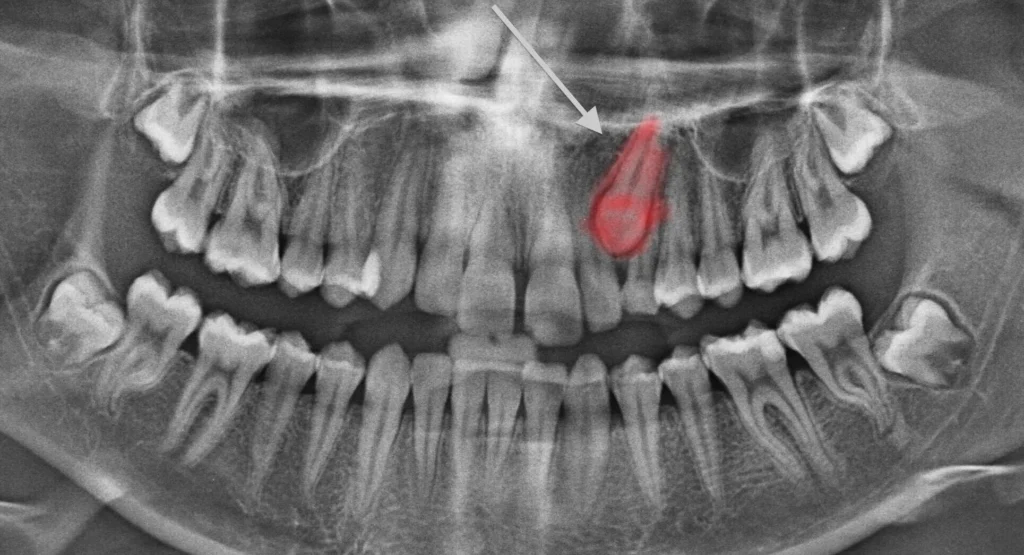

Radiographie Panoramique

La panoramique est l’examen de débrouillage incontournable. Elle permet d’évaluer :

- La position dans le plan vertical (hauteur d’inclusion)

- L’axe général de la dent

- Les rapports avec les dents voisines (résorptions ?)

- La présence d’odontomes ou de germes surnuméraires

Limite importante : la position vestibulaire ou palatine ne peut pas être formellement déterminée sur cet examen seul.

Investigations : La panoramique confirme l’inclusion canine 13 en position haute, axe oblique. Le CBCT localise la canine en position palatine, avec son apex en regard de la racine de l’incisive latérale sans résorption visible.